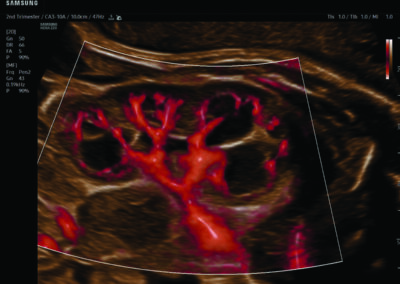

Procedural Services

Comprehensive, advanced and expert MFM care for high-risk pregnancies

- Fetal anomalies